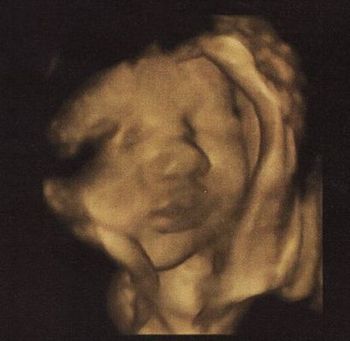

Ja és a fej 2mm-t nőtt, a combcsont 1-et (mármint a múlt heti kórházi adatokhoz képest), ami dicséretes, de így is le van maradva 3 héttel. Megint jött a kórházba befekvéssel, én meg közöltem, hogy még mindig nem kérek belőle.

Totál elegem van, jó lenne már túllenni az egészen. Ja és a flowmertria, nst jó lett, nem lehet semmibe belekötni azon kívül, hogy kicsi a gyerek feje, de könyörgöm azzal meg mit lehet tenni??